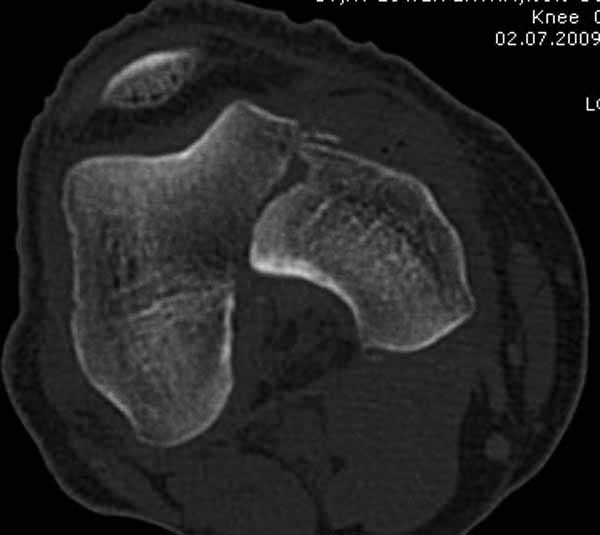

>Сразу не обратил ваше внимание именно на это, что сломаны оба мыщелка, и больший является именно медиальным мыщелком

А теперь по поводу лечения перелома. Среди всех чрез/меж-мыщелковых переломов в 38% сопровождются переломом в корональной плоскости, т.е перелом Hoffa. Nork et al, J Orthop Trauma, 87:564, 2005.

По снимку вроде одиночный простой мыщелковый перелом, и такой внутрисуставной перелом не обязательно дистрагировать на скелетном вытяжении, потому что не не нарушается непрерывность колонны с одной стороны. И для таких простых переломов подойдет любой метод: 95 градусная пластина, Lat. Condylar Butress пластина или ретроградный гвоздь. А для особых энтузиастов которые желают антеградную фиксацию, возможно легко найти трохантер у алкоголиков или дистрофиков. А вот у откормленных Макдональдскими гамбургерами? Если поискать у них тоже можно найти, но стоит ли?

У больных как в этом случае, с вовлечением двух мыщелков правильно, что сделали вытяжение до операции. Здесь имеется флексионный компонент на другой стороне, и я бы рекомендовал операцию делать из двух доступов. Сперва фиксировать медиальную колонну custom made пластиной, обычно 1/3 тубулярной пластиной в 4.5 мм, потому что пока производители опаздывают с медиальной пластиной.